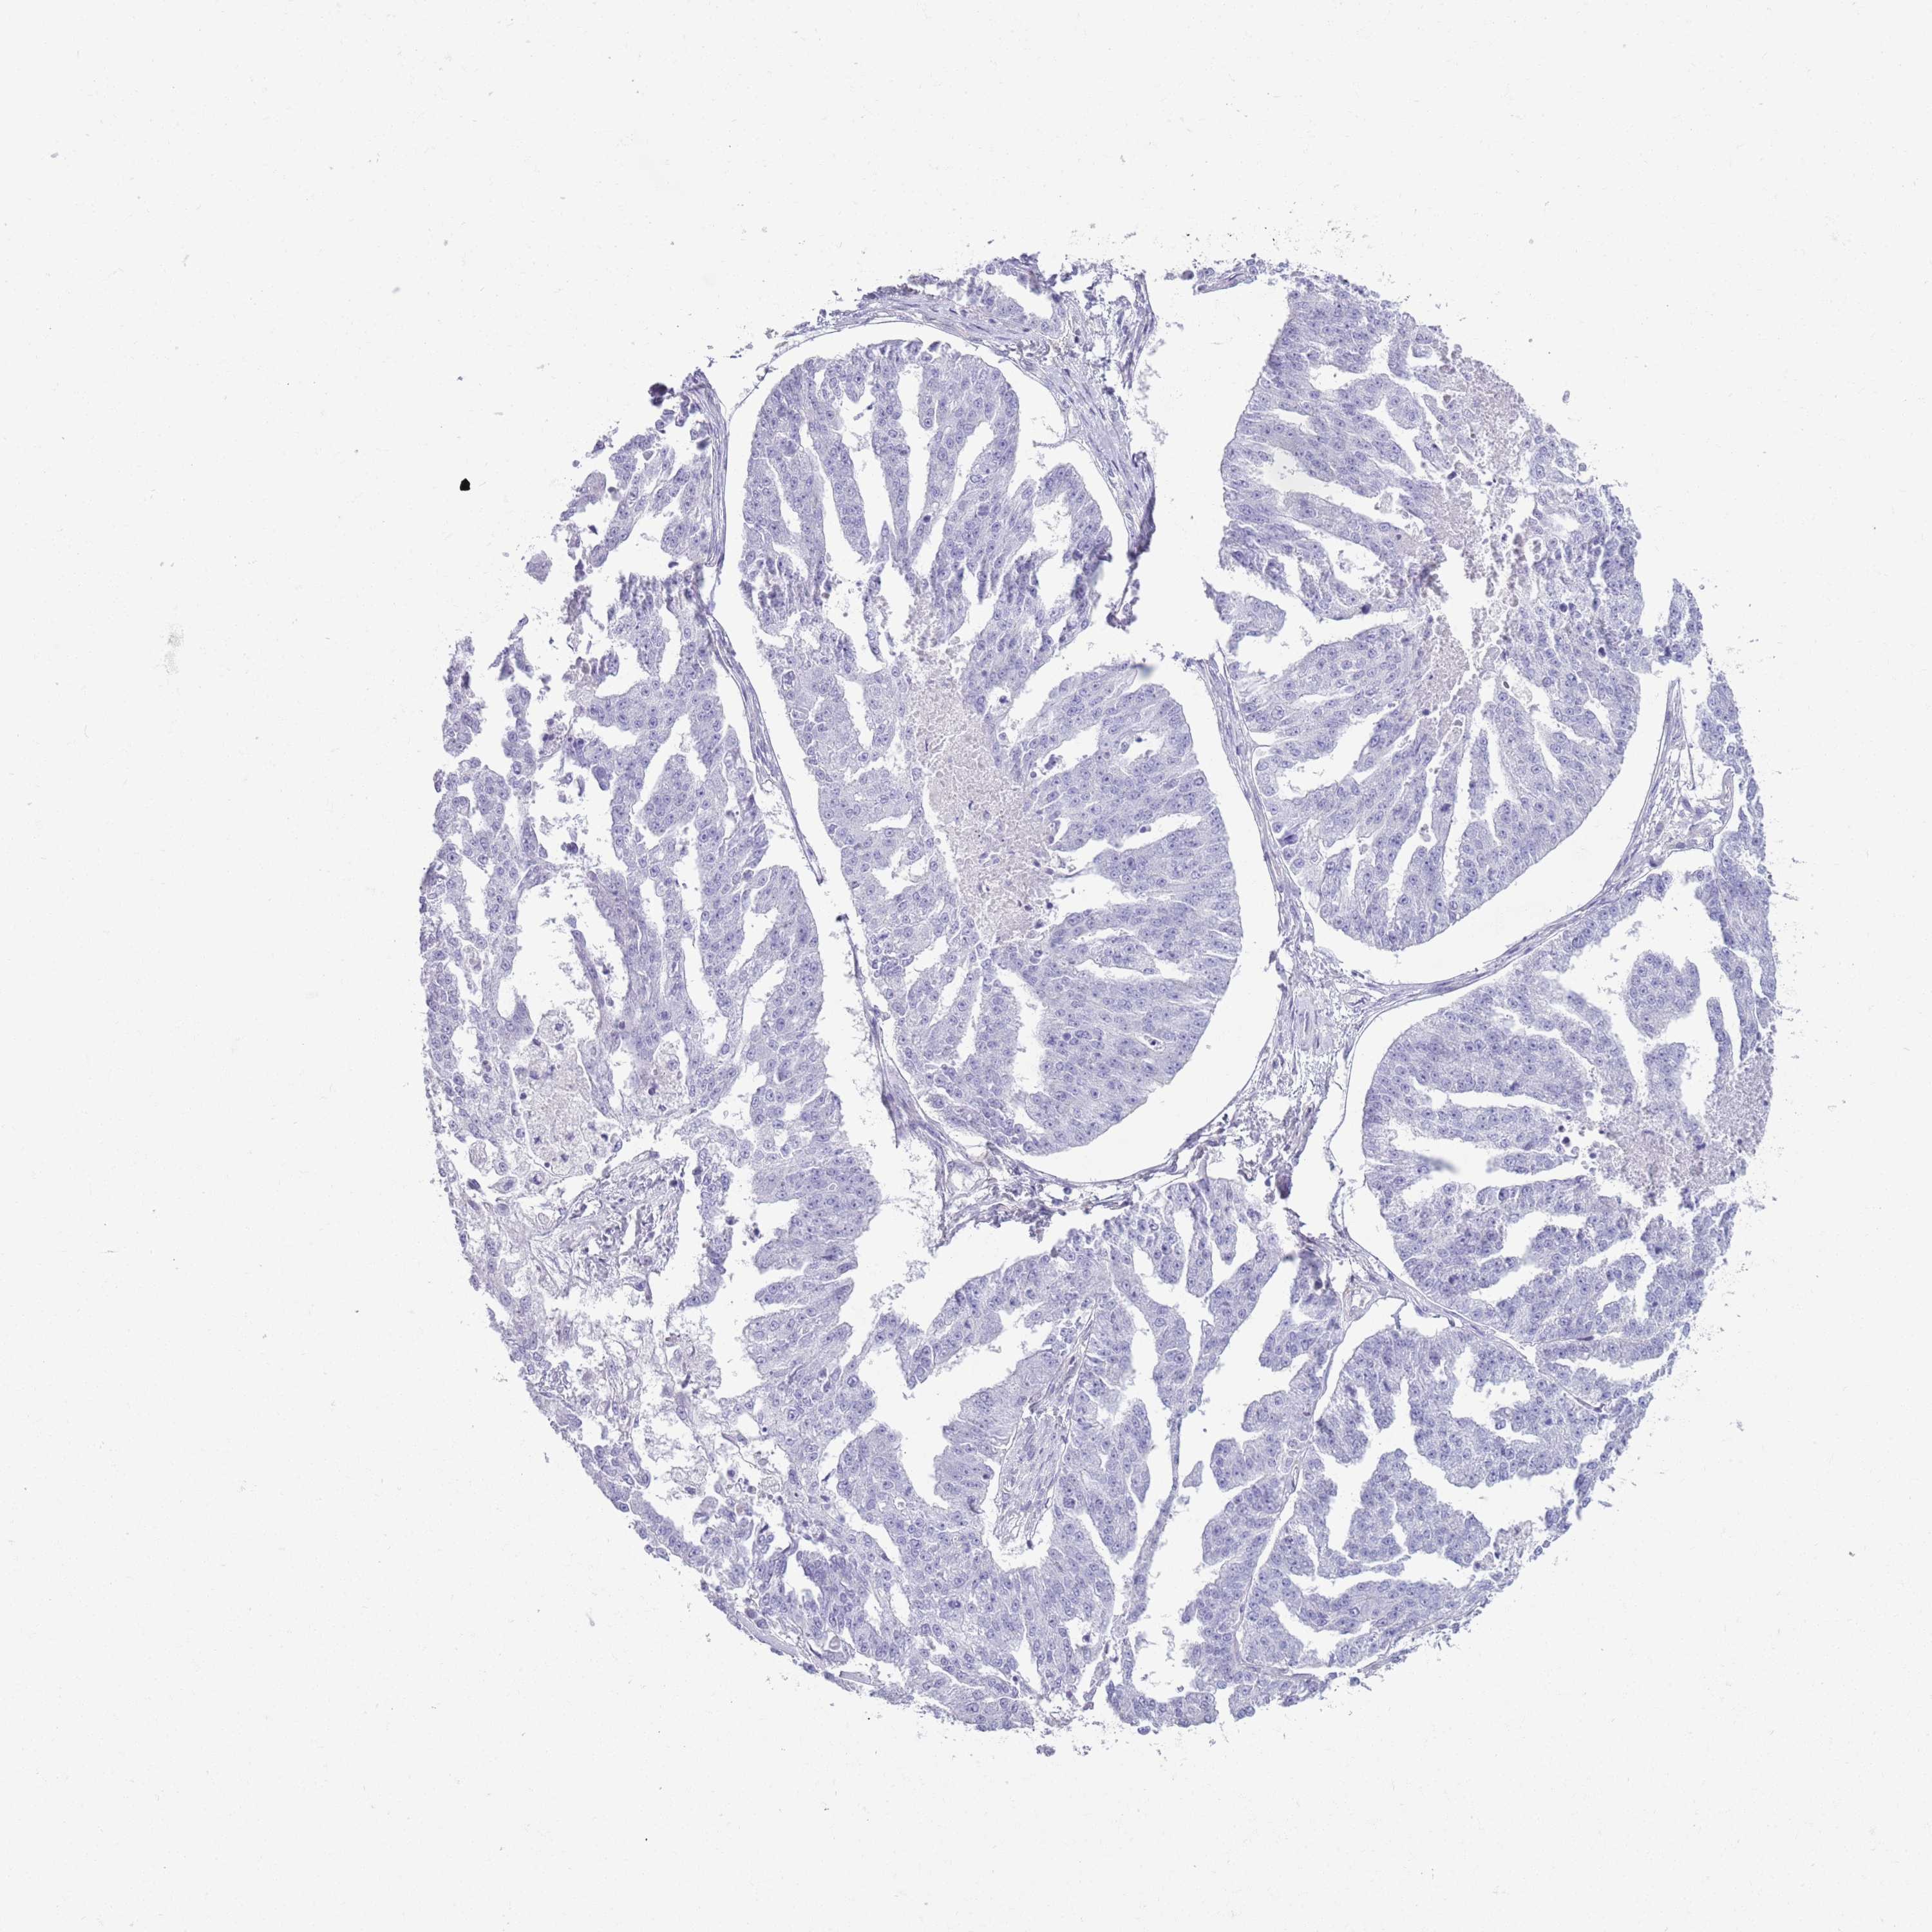

OVARIAN CANCER - Protein expressioni

A mouse-over function shows sample information and annotation data. Click on an image to view it in a full screen mode. Samples can be filtered based on level of antibody staining by selecting one or several of the following categories: high, medium, low and not detected. The assay and annotation is described here.

Note that samples used for immunohistochemistry by the Human Protein Atlas do not correspond to samples in the TCGA dataset.

Antibody stainingi

Antibody staining in the annotated cell types in the current human tissue is reported as not detected, low, medium, or high, based on conventional immunohistochemistry profiling in selected tissues. This score is based on the combination of the staining intensity and fraction of stained cells.

Each image is clickable and will lead to virtual microscopy that enables deeper exploration of all samples and also displays staining intensity scores, fraction scores and subcellular localization as well as patient and tissue information for each sample.

Antibody HPA041301

Antibody HPA044239

Staining

High

Medium

Low

Not detected

Intensity

Strong

Moderate

Weak

Negative

Quantity

>75%

75%-25%

<25%

None

Location

Nuclear

Cytoplasmic/membranous

Cytoplasmic/membranous,nuclear

Cystadenocarcinoma, serous, NOS

Carcinoma, endometroid

Cystadenocarcinoma, mucinous, NOS

Carcinoma, NOS